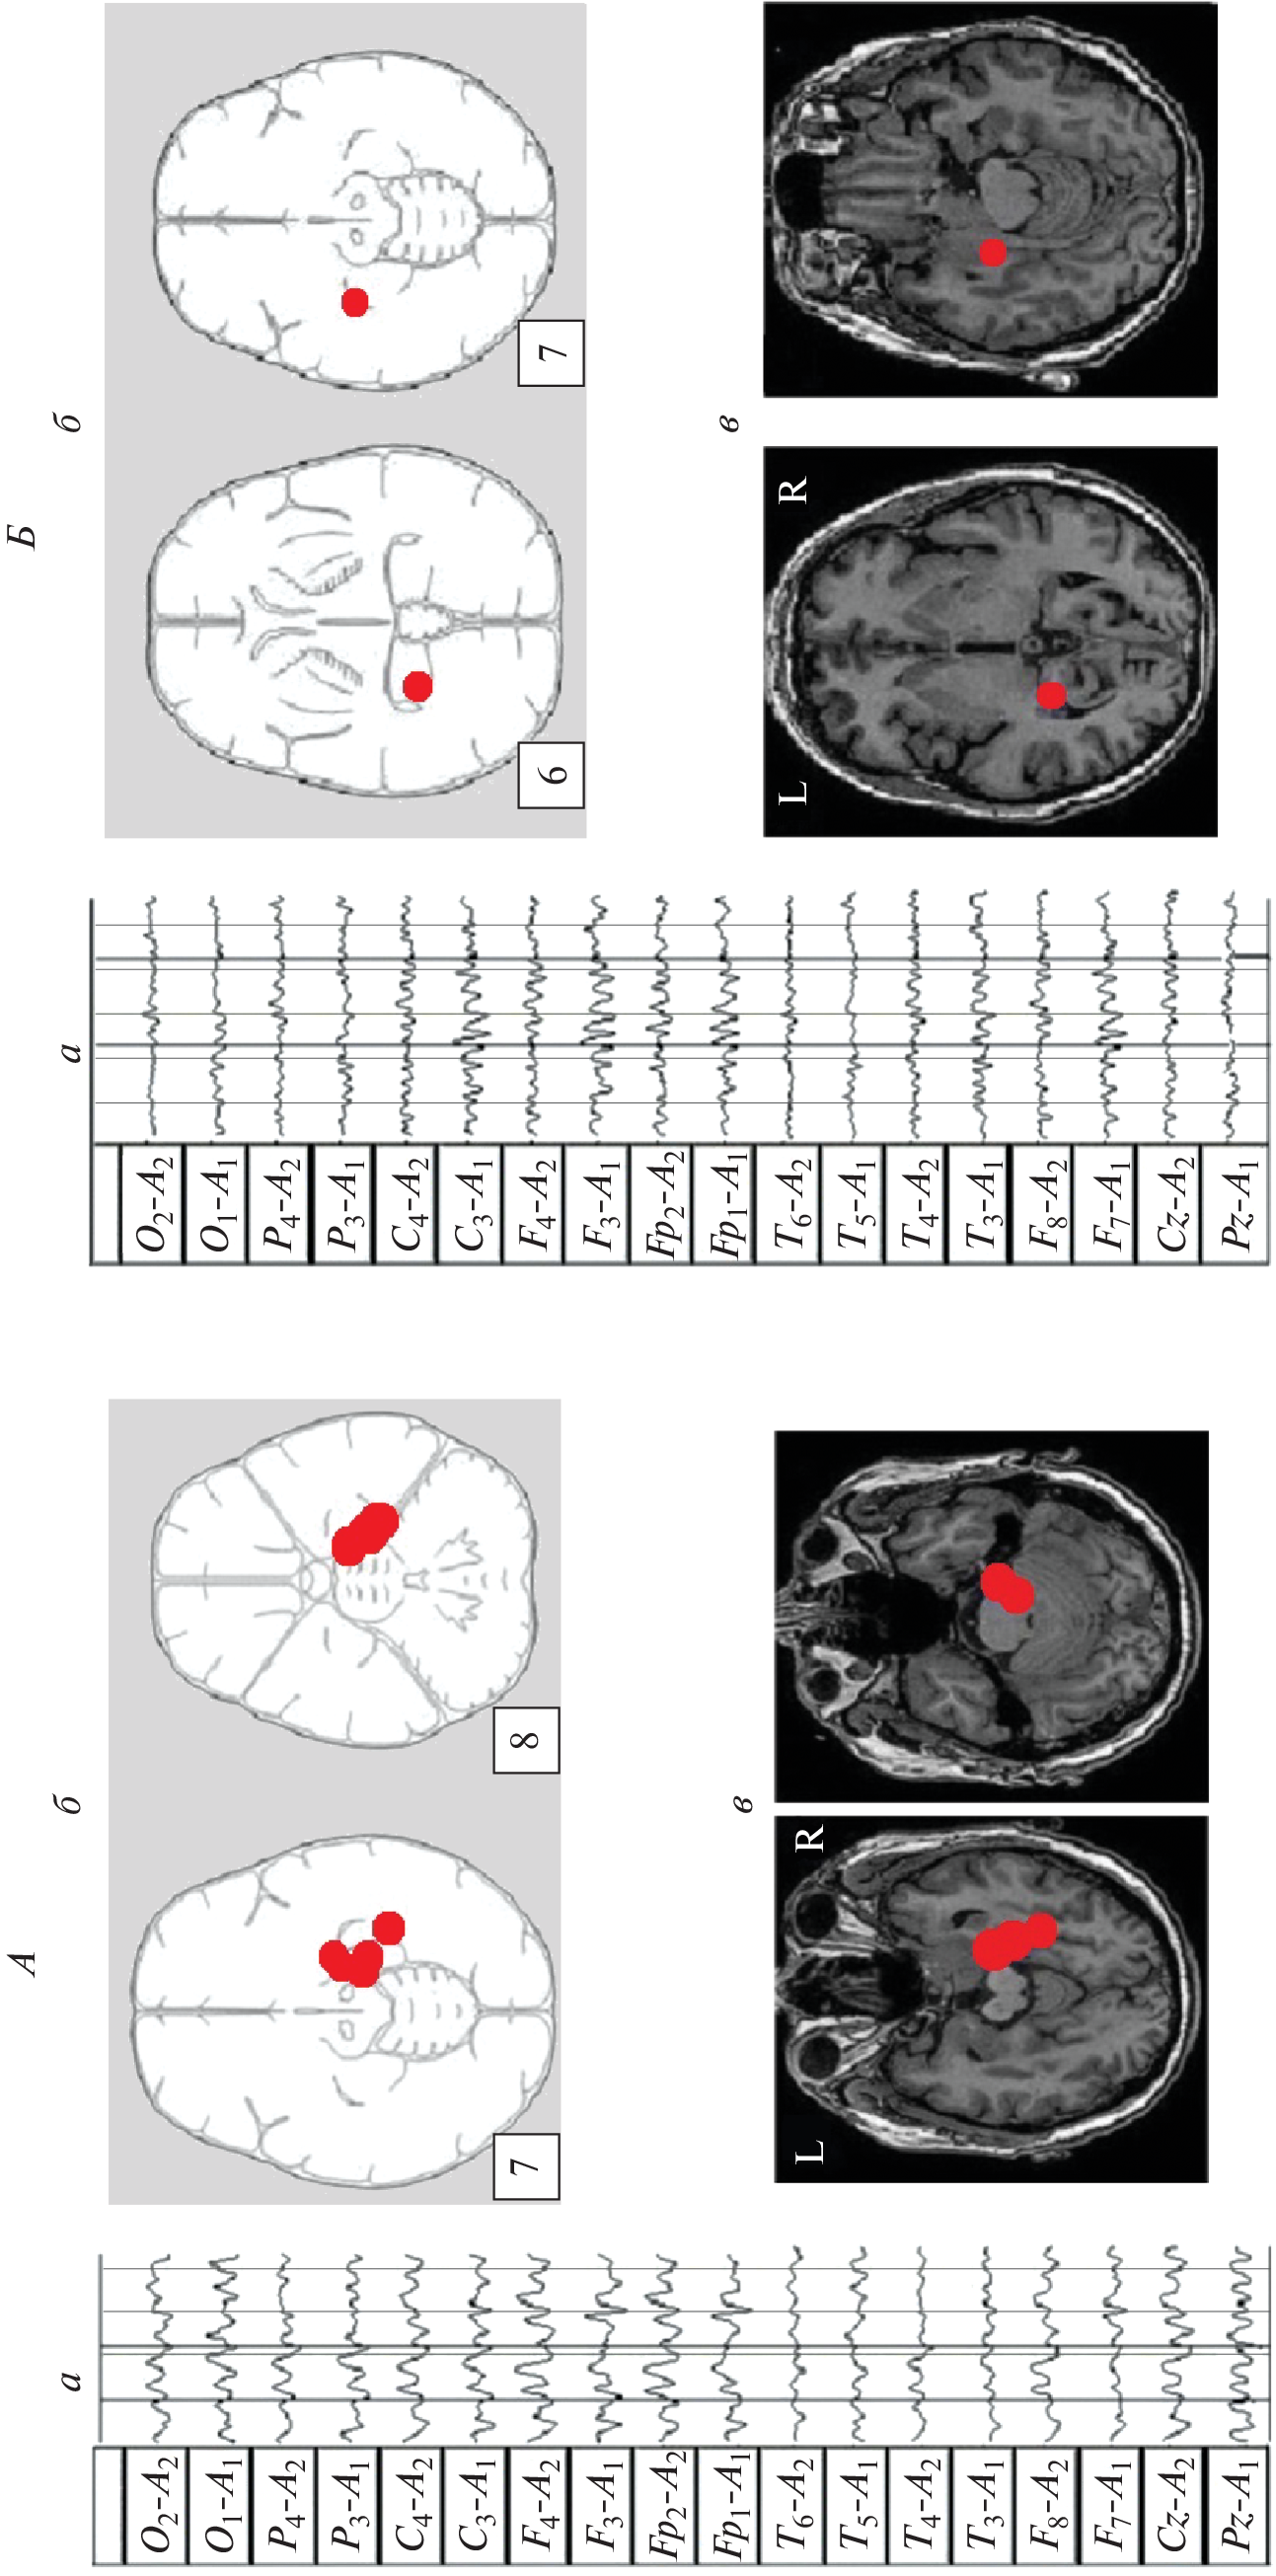

We studied the features of EEG and visual memory processes in 27 patients with a mediobasal regions extracerebral tumor of right and left hemispheres. According to neuroimaging (MRI) and morphometry, the degree of hippocampus involvement in pathological process was assessed. The predominant concentration of irritative-epileptiform signs in the affected hemisphere, as well as the presence of atypical alpha-rhythm episodes in the tumor projection zone, were classified as EEG markers of tumor compressive effect on the hippocampus. Signs of non-identical involvement of the right and left hippocampi in the pathological process were found in the form of a predominance of irritative signs in the left hemisphere throughout the group as a whole. Equivalent dipole sources (EDS) of atypical alpha rhythm are more confined to hippocampal structures than irritative EEG patterns. Neuropsychological testing of visual memory did not reveal significant disturbances in memory processes at this stage of the disease.

- Болдырева Г.Н. Атипичные формы церебральной альфа-активности при поражении регуляторных структур мозга человека // Физиология человека. 2018. Т. 44. № 3. С. 14. Boldyreva G.N. Atypical forms of cerebral alpha activity when human brain regulatory structures are damaged // Human Physiology. 2018. V. 44. № 3. P. 246.

- Болдырева Г.Н., Шарова Е.В., Коптелов Ю.М. и др. Исследование генеза патологических паттернов ЭЭГ при опухолевом и травматическом поражении мозга человека // Физиология человека. 2005. Т. 31. № 1. С. 24. Boldyreva G.N., Sharova E.V., Koptelov Yu.M. et al. Study of the genesis of pathological EEG patterns in tumor and traumatic lesions of the human brain // Human Physiology. 2005. V. 31. № 1. P. 18.

- Фролов А.А., Болдырева Г.Н., Коптелов Ю.М. Поиск источников патологической альфа-активности ЭЭГ человека при поражении лимбических структур // Журн. высш. нерв. деят. им. И.П. Павлова. 1998. Т. 48. № 4. С. 687. Frolov A.A., Boldyreva G.N., Koptelov Yu.M. [Sources of pathological EEG alpha-activity in patients with lesions of limbic structures] // Zh. Vyssh. Nerv. Deiat. Im. I.P. Pavlova. V. 48. № 4. P. 687.